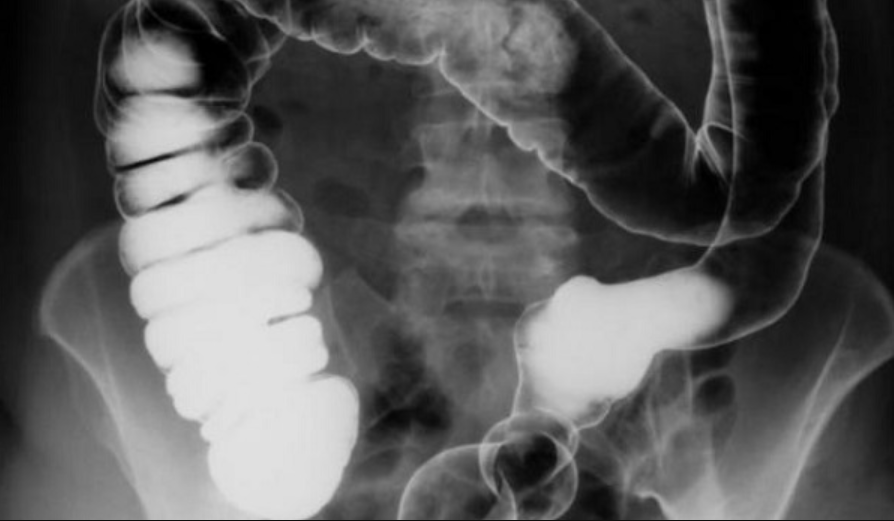

5. Chụp X-quang đường tiêu hóa dưới (khung đại tràng) có cản quang

Các phương pháp chẩn đoán hình ảnh đại tràng tiến triển theo thời gian, khiến vai trò và số lượng chụp X - quang đại tràng cản quang ngày càng giảm . Tuy vậy, chụp đại tràng cản quang vẫn được sử dụng ở các khoa chẩn đoán hình ảnh có truyền thống trên thế giới để đảm bảo bệnh nhân nhận được dịch vụ chẩn đoán và điều trị chất lượng cao.

5.1. Chỉ định và kỹ thuật chụp cơ bản

Có hai kỹ thuật chủ yếu chụp đại trực tràng thụt baryt là cản quang đơn (single contrast) và cản quang kép (double contrast) để bộc lộ các tổn thương niêm mạc, tổn thương trong thành đại tràng và tổn thương đè ép từ ngoài. Chụp cản quang đơn thường được dùng để đánh giá tắc đại tràng, rò đại tràng, chụp cho người già, bệnh nhân nặng hoặc yếu sức. Chụp cản quang kép thường được dùng để phát hiện các tổn thương nhỏ (

5. 2. Giải phẫu xquang bình thường

Đại tràng là phần cuối cùng của ống tiêu hoá, dài 1,4 m tới 1,8 m, gồm có: manh tràng và ruột thừa ở hố chậu phải, tiếp theo là đại tràng lên đi sát thành bụng phải tới mặt dưới gan phải, đại tràng ngang quặt ngang sang trái tới lách, đại tràng xuống đi dọc thành bụng trái tới hố chậu trái, đại tràng sigma đi tới chậu hông bé, trực tràng đứng thẳng giữa trước xương cùng. Đại tràng có hai chỗ gấp khúc là: góc đại tràng phải hay góc gan và góc đại tràng trái hay góc lách. Đại tràng lên và đại tràng xuống tương đối cố định.

Chụp X quang đại tràng dùng thuốc cản quang là phương pháp thường được bác sĩ xem xét trong chẩn đoán nhiều bệnh lý đại tràng, trong đó có ung thư đại tràng. Trước khi chụp đại tràng cản quang, đại tràng cần được làm rỗng để đảm bảo hình ảnh phim chụp không bị mờ và không có sự nhầm lẫn giữa các tổn thương ở đại tràng. Ngoài ra, để kết quả chụp chính xác nhất, người khám cũng nên áp dụng chế độ ăn đặc biệt đó là chế độ ăn không gây tồn đọng trước 2 ngày, đồ ăn không nhiều xơ, lên men. Bệnh nhân cũng sẽ được dùng thuốc nhuận tràng và thụt tháo kĩ 2 lần trước khi làm thủ tục chụp vài giờ.

Người khám được chụp với nhiều tư thế khác nhau, hình ảnh của các đoạn đại tràng như sigma, trực tràng, góc lách trái, góc gan, manh tràng, đại tràng lên... được ghi lại để bác sĩ đánh giá tình trạng tổn thương của mỗi người.